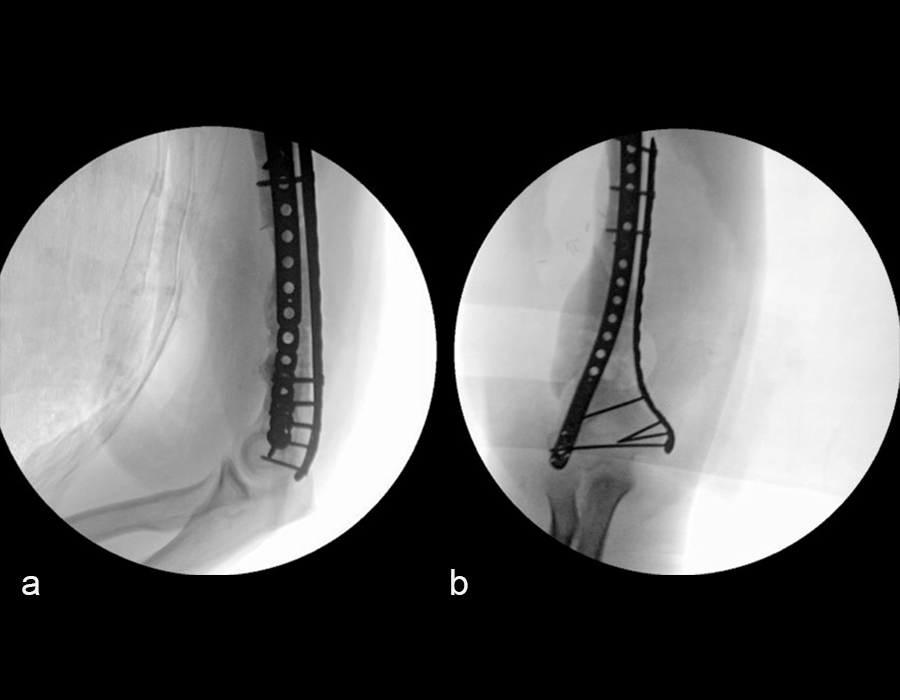

In a first stage, the distal humerus was debrided and devitalized bone was resected, leaving an 8cm defect into which a cement spacer was placed. New plates were inserted to stabilize the fracture (Fig 17 and Fig 18). Cultures taken in the OR were negative.

The second stage of surgery took place in October 2022. The cage was inserted (Figs 20-22) and filled with ~20cc autograft obtained by RIA of the femur, 30cc allograft and 3cc BMAC.